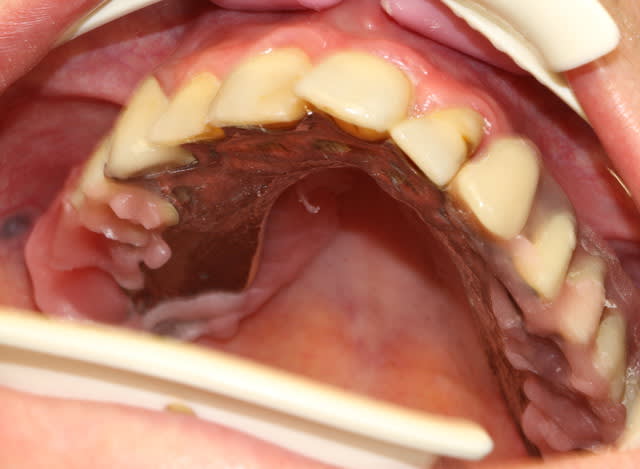

je continue l'entrainement :

voila Marc j'ai recadré!

Le sujet : ajuster un stellite après la pose des vis de cicatrisation sur 8 implants.

Rien de mirifique, juste un "bricolage" pour que la patient puisse manger.

incroyable tu fais même de l'expansion sur les chassis de stellite

trop fort

et je remarque que tu as abandonne le fitt au profit de GC

j'ai bon ?